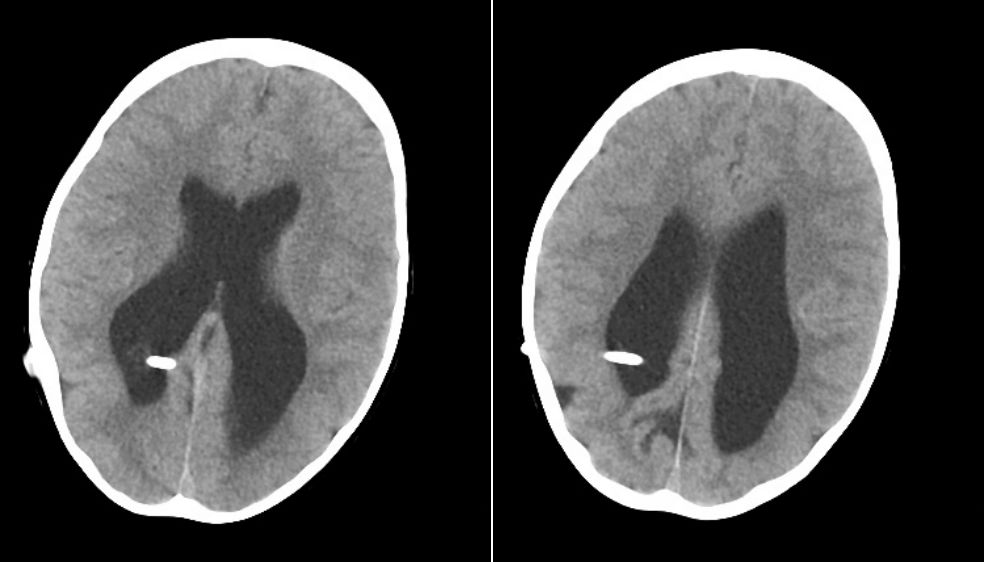

病例1:术后1天CT,见囟门已凹陷。

术后2年半(2015.7.12)复查CT:脑室形态较前好转缩小,脑实质发育良好。

术后4年(2016.12.29)复查CT如下:同前相仿。